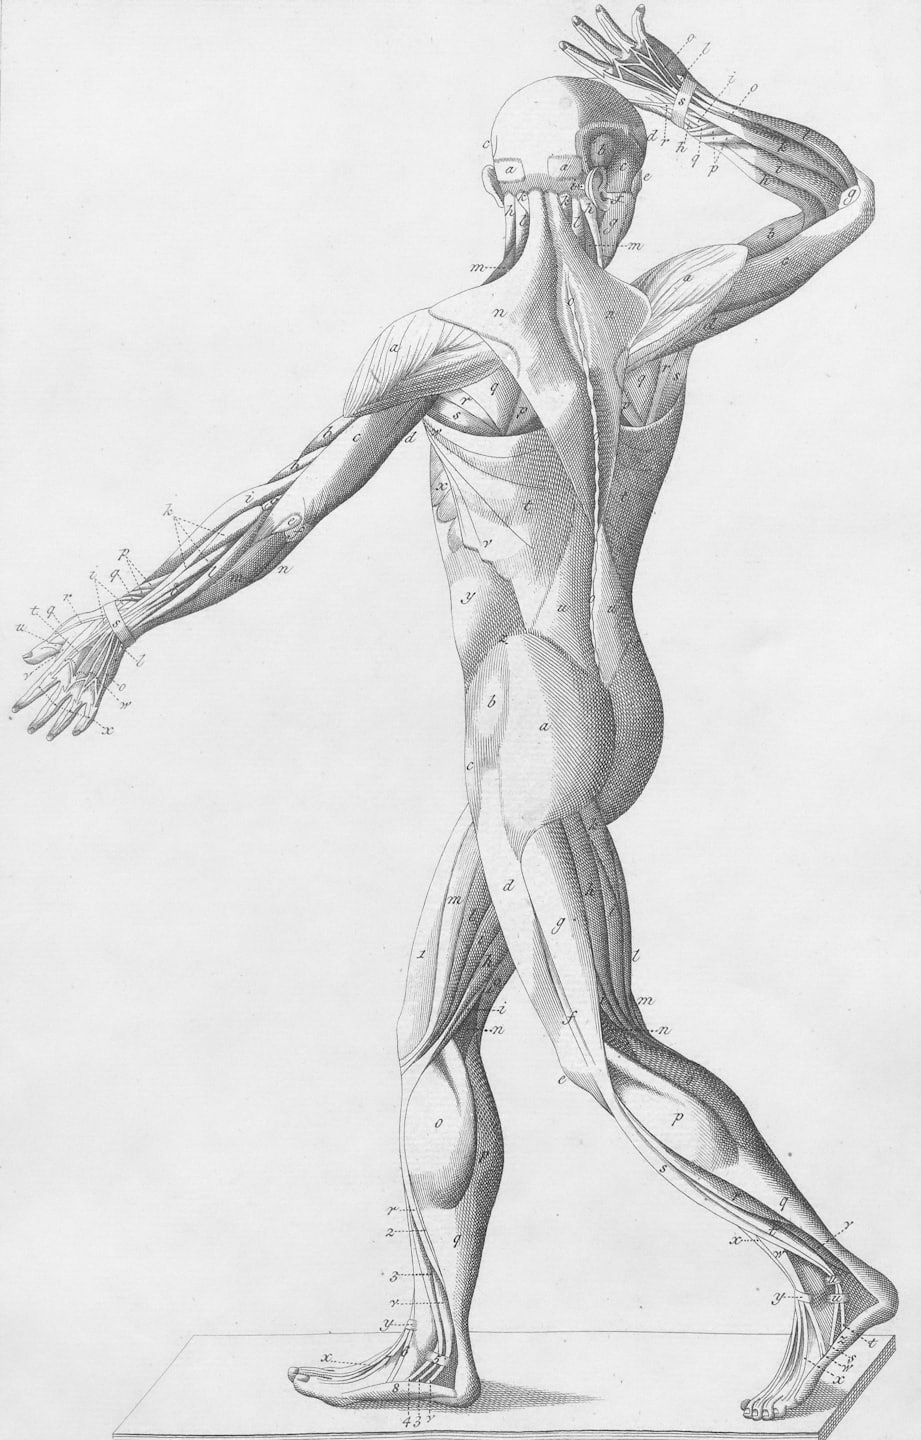

El desarrollo de unos brazos masivos y funcionales depende de la manipulación precisa de los momentos de fuerza. En este análisis de ingeniería, diseccionamos la biomecánica de flexión y extensión de codo para asegurar que cada grado de movimiento genere la máxima tensión mecánica, protegiendo siempre la salud de tus tendones.

Aquí analizamos detalladamente la biomecánica de los brazos, mostrando cómo optimizar la hipertrofia de bíceps y tríceps con precisión científica.

Estudio detallado de la flexión y extensión del codo para mejorar la función muscular.

Aprende cómo manipular momentos de fuerza para maximizar la flexión de codo.

Aquí encontrarás imágenes que ilustran la biomecánica y técnica para maximizar la hipertrofia muscular.